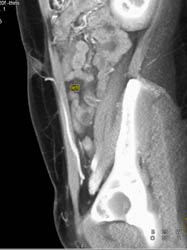

DIEP Flap Planning